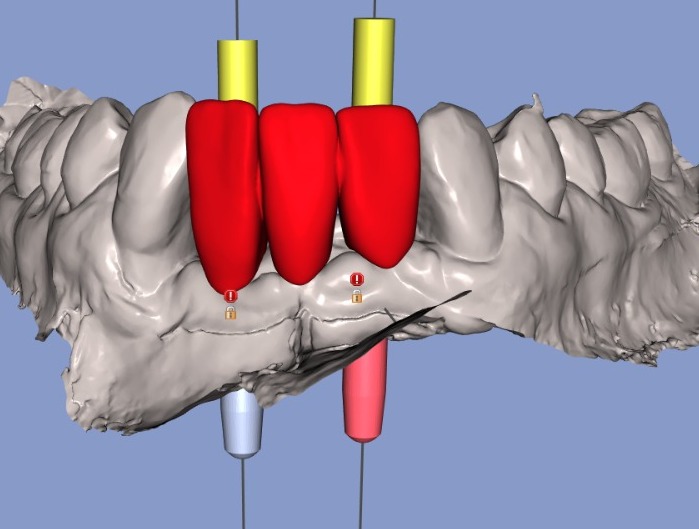

La cirugía de implantes guiada es un procedimiento moderno y preciso que permite colocar implantes dentales en el hueso utilizando una guía quirúrgica personalizada.

Esta guía actúa como un “molde” que indica con exactitud el lugar, la profundidad y el ángulo correctos donde se debe colocar cada implante.

Para su planificación y confección es necesario un estudio detallado a partir de una Tomografía Cone Beam (TCCB) y un escaneo digital de la boca.